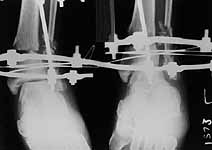

Thank you all for the kind responses. Kindly find attached the post op picture. I did an Ilizarov ring fixation which extended to the calcaneum. There was multiple small areas of partial thickness skin necrosis anteriorly and laterally which required split thickness skin graft.

Ilizarov device is a good choice, but I'm concerned about the valgus angulation (> 15degrees ?).

1. The reduction is in Valgus. Which you could correct on the Ilizarov and

2. The Lateral Malleolus is about 6mm superior to its normal position, which I don't know how you could correct.

Why connecting rods are bent?

As Dr Finlayson commented the fragments are malaligned. The combination of wires and pins in the middle ring makes correction at least inconvenient though of course it is always possible to re-assembly the frame and include hinges.

It would be quite enough to have either a 6 mm half pin or a olive wire inserted in frontal plane just above the fracture. The pin or wire would help to move the distal part of the shaft laterally (and a bit back) to align the fracture.

See an example of the suitable assembly. The injury is not so severe as in your case but the fracture pattern dictates a quite similar mounting. Since in your case the distal fragment is even larger than in the example there is no need to use foot extension as dr M. Parihar said. A foot support looks enough.

To give the follow up on this patient: A repeat X-ray showed the talus subluxating laterally. A dynamic inversion and eversion strain view pictures showed the lower tibio-fibular syndesmosis opening out. The frame was re-adjusted. Fracture site compressed and valgus corrected. A syndesmotic compression was achieved by adding a washer to the olive and pulling the comminuted lateral malleolus medially. another olive with washer given through talus lateromedially. The equinus that you may see has been corrected. Pictures attached. would welcome critical comments.